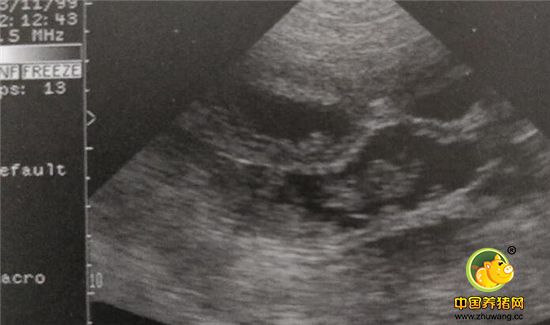

不同时间段胎儿在母猪体内的样子——B超B超母猪的怀孕情况方法

注意观察B超探头的摆放位置带盖,大概位于倒数第一对和第二对乳头之间。

这是母猪妊娠21天后,仔猪在子宫内的形状。

该图为母猪妊娠23天左右胎儿的图像。此时孕囊已经打了不少,用B超检测很容易发现。

这是妊娠35天左右胎儿在母猪子宫内的成像,子宫壁和胎盘变厚,并且紧密的镶嵌在一起而,胎儿在在其中间。